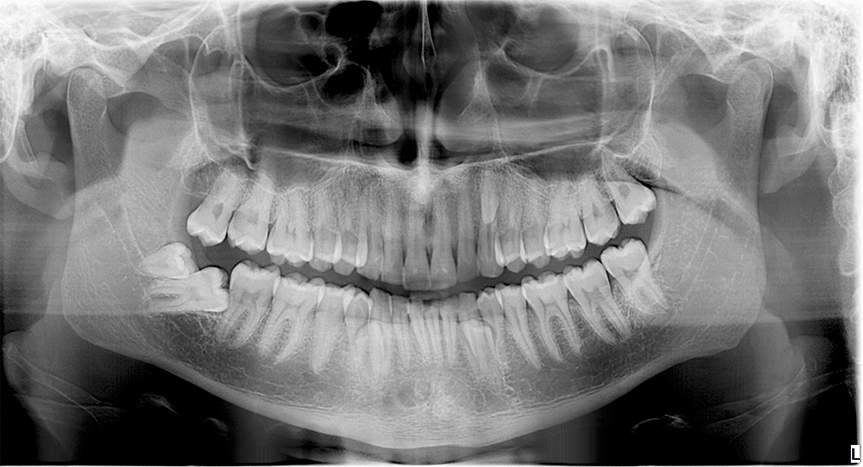

Paziente di anni 25.

L’indagine richiesta aveva come quesito diagnostico la mancata eruzione di 48.

L’immagine ha mostrato la presenza di numerosi elementi sovrannumerari.

Il primo si proietta sul terzo medio- distale radicolare di 23, altri due a livello interprossimale fra 33-34 e 43-44 e altro distalmente a 48 incluso quasi trasverso.

La corona di 48 entra in conflitto con la giunzione corono-radicolare distale di 47 che presenta iniziale minus. La presenza degli elementi sovrannumerari nel I, II e III quadrante non ha determinato problematiche a livello degli elementi definitivi che sono tutti correttamente erotti.

Per la corretta localizzazione spaziale di 48 e 49 ed i loro rapporti con il canale alveolare è necessario approfondimento di indagine con TC cone beam.